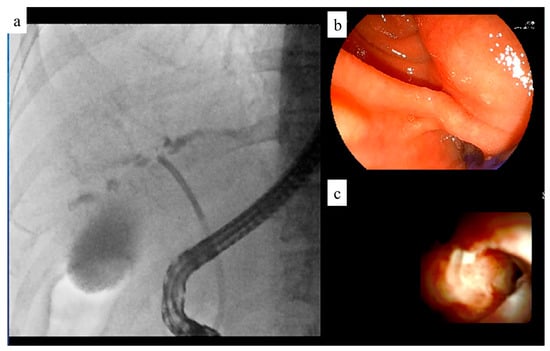

6. Recording System

Previously, fluoroscopic videos were recorded with a reduction in the number of scanning lines from 1000 to 500, resulting in lower definition. To address this, we developed the VC-1000 recording device, manufactured by Fujifilm, which maintained 1000 scanning lines for high-definition recording. The VC-1000 can record endoscopy and fluoroscopy images simultaneously.

The upgraded VC-2000, which can record up to four systems of video information simultaneously, has since been introduced (Figure 9). The VC-2000 can simultaneously record endoscopic, fluoroscopic, and EUS images as well as images from video cameras installed in the examination room. This allows the endoscopist to review the operation images after the examination. The ability to review video images recorded simultaneously facilitates communication between instructors and junior endoscopists.

Figure 9. Recording system. This system can record multiple images simultaneously. (a) Fluoroscopic image. (b) Endoscopic image. (c) Peroral cholangioscopic image.